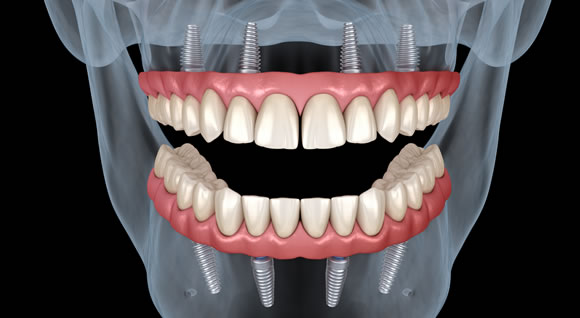

最終ブリッジを取り付けた状態

オールオン4は、埋め込むインプラントの数が最少4本*。骨の移植なども必要ありません。抜歯からインプラントの埋め込み、仮歯の装着まで、1日で行うことが可能になりました。

オールオン4は、奥のインプラントを骨のある部分へ斜めに埋め込み、力を広く均等に配分することにより、最小4本*のインプラントですべての人工の歯を支えることに成功。従来の不安要素を解消することができました。手術や費用の負担を必要最小限に抑えた新しいインプラント治療法、それがオールオン4です。

インプラントの埋め込みから約6ヶ月後に、高度が強く、美しい仕上がりの最終ブリッジと交換します。

最終ブリッジを取り付けた後はご自分の歯のようになんでも噛めるようになります。

▲強度が高く、美しい仕上がりの最終ブリッジ